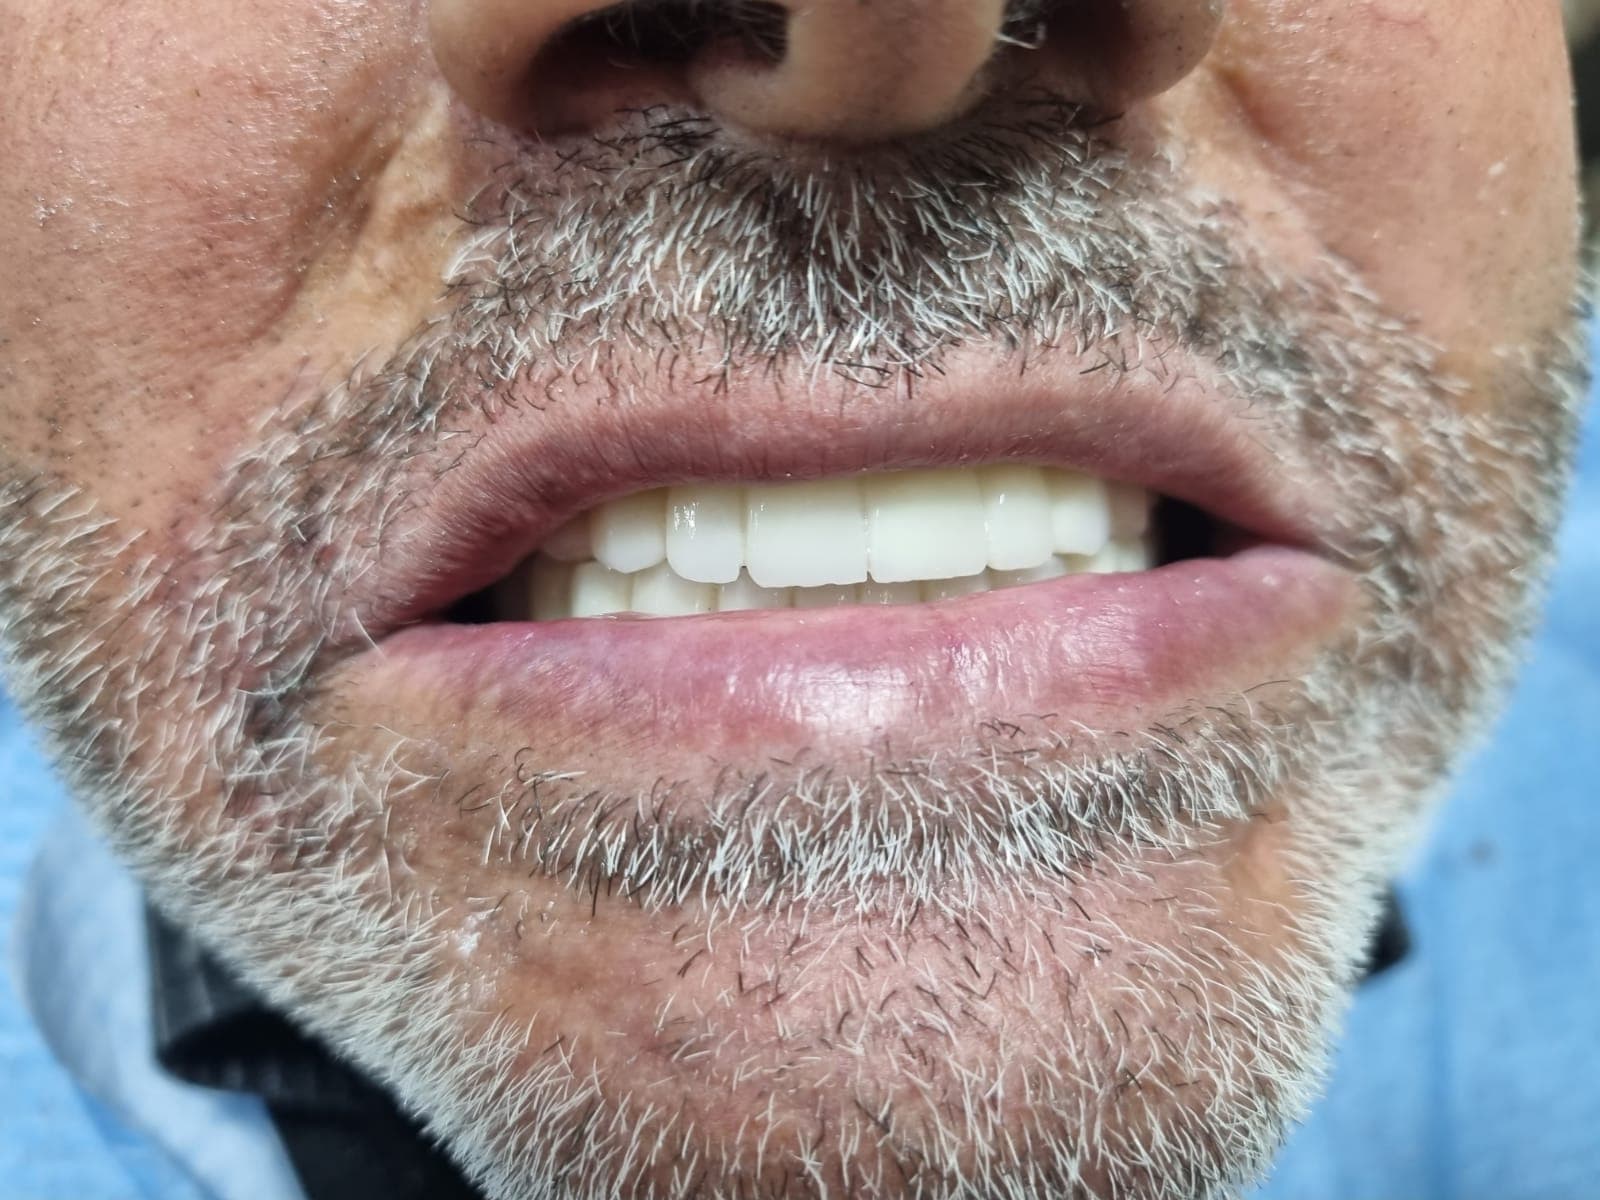

ЗаписатьсяРеальные случаи из практики клиники. Наведите на фото и нажмите кнопку, чтобы увидеть состояние до лечения.

Полная эстетическая реставрация передних зубов

Имплантация и установка несъёмного протеза

Восстановление жевательной функции

Все фотографии опубликованы с письменного согласия пациентов.

Восстановленная функция и эстетика зубного ряда

Финальный вид после имплантации и протезирования